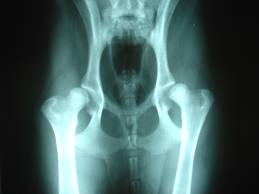

Out of more than 3100 Birmingham Hip Resurfacings over the past 12 years, we had 10 patients (1 in 300) who developed a local adverse reaction like this. In most of these there was only a collection of fluid around the hip joint nearly 10 years or more after their original operation. They complained of groin pain or discomfort. A few developed swelling of the foot or ankle because of the collection of fluid above. In many cases there were subtle X-ray changes, although not in all. In addition, in a couple of cases there was osteolysis (bone resorption). Other Centres have reported muscle damage or pressure effects on the nerves or blood vessels from the fluid, fractures or dislocations.

If a person presents with a history suggestive of a pseudotumor, he/she needs to be examined by an orthopaedic surgeon and undergo X-rays, a special multi-slice CT scan and some blood tests in order to establish the diagnosis. The CT scan must be able to reduce artefact from the metal in order to provide any useful information. In some cases it may be necessary to exclude infection by aspiration of the hip joint. If it is indeed a pseudotumor then a revision operation to convert the resurfacing into a total hip replacement with a non-metal-metal bearing will have to be performed.